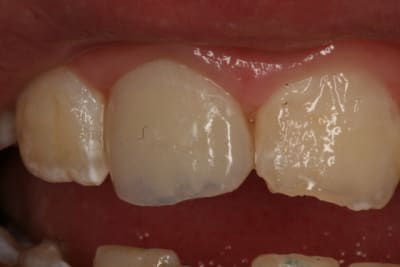

Regardez ce que je viens de recevoir de mon prothésiste habituel.

Vous conviendrez que le résultat n'est pas terrible, mais est assez représentatif de ce que je reçois.

A chaque fois, je met en cause mes piètres talents de prise de teinte, mais vous constaterez sur la deuxième photo que j'étais quand même plus proche que lui.

Alors est-ce qu'on arrive aux limites des CCM ?

Ou faut-il que je change de prothésiste (suggestions sur Paris/RP en MP, merci) ?

'tain là on est dans le B1 en plus elle est hyper opaque

Le teintier que je présente est un A3,5.

Merci de me confirmer que je ne suis pas un chieur...

Au niveau opacité c'est à peu près ce que j'ai régulièrement.

Je me disais, pour du moyen-haut de gamme, tu ne peux pas avoir la lune. Vos 45 euros sont très éloignés du prix payé.

c'est une ccm monocouche avec un peu de maquillage au collet ,maqquillage qui finira par s'en aller..

trop globuleuse et epaisse (maisquelle epaaisseur lui as tu laissé?)

et pas très bien sculptée(mais qu'y a t'il en face?)